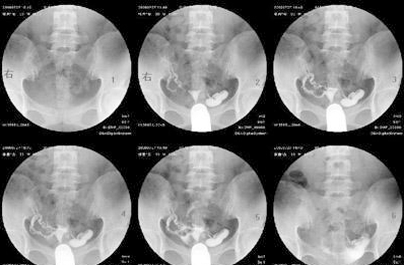

输卵管造影是检查女性输卵管是否通畅的一种方法,做输卵管造影前一定要了解造影什么时候做最好及术前术后的注意事项,输卵管造影虽然只是一种检查方法,但是对于女性的身体还是存在危害的可能,所以做输卵管造影前一定要了解清楚。

输卵管造影检查准确性高,并且安全无副作用,还可以在治疗的同时对轻微的输卵管粘连有一定的治疗作用。但是一定要选择适合的时间做检查,这样检查的结果比较准确,而且对人体的伤害也比较小。